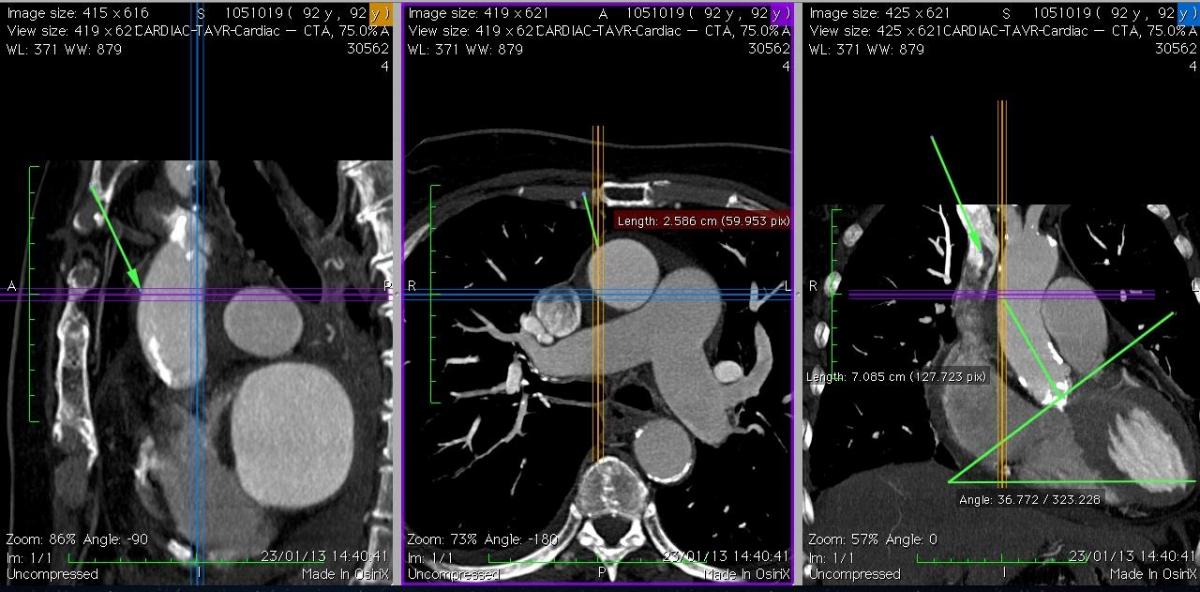

4. Trans-Aortic Valve Replacement with Edwards Sapien-Ascendra 3 Mark Russo Paolo Tartara |